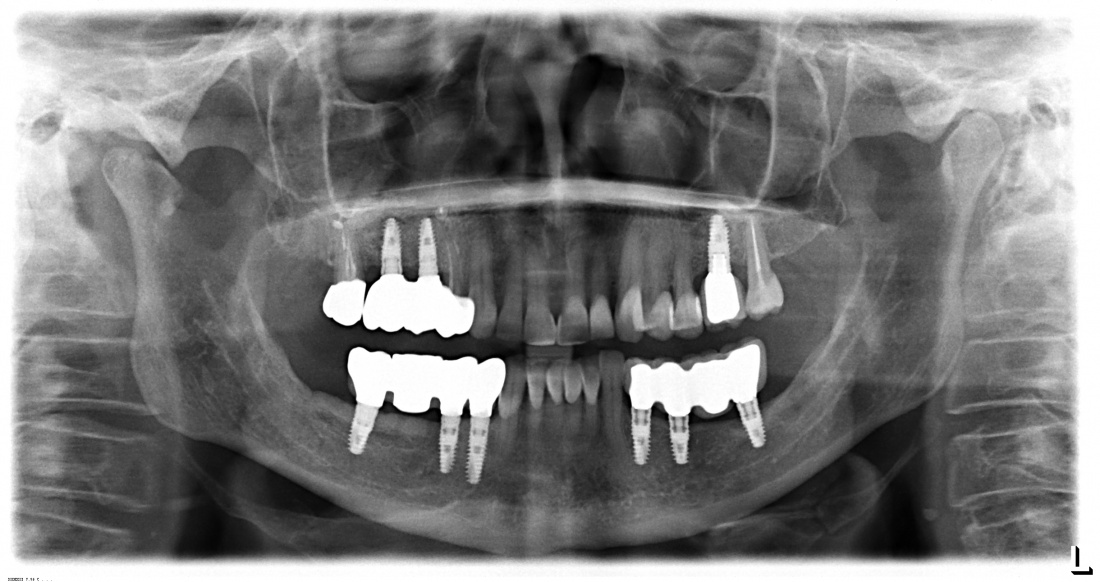

Через 4 месяца мы делаем контрольный рентгеновский снимок:

И готовимся к постоянному протезированию. Для этого мы открываем интегрированные имплантаты и устанавливаем на них формирователи десны. За пару недель они сформируют вокруг платформ имплантатов десневую манжету, которая защитит их от внутриротовой инфекции. Понятное дело, что после этого нужно откорректировать протез, что я и сделал.

Состояние имплантатов, протетики, десны вокруг имплантатов более, чем удовлетворительное. Да, хотелось бы картинку пофотогеничнее, но Елена не испытывает с протетикой никаких проблем, гигиена удовлетворительная, качество жизни на уровне — чего еще желать? Вот контрольная ортопантомография через три с половиной года после протезирования:

Собственно, больше пяти лет после остеопластики и имплантации, через три с половиной года после протезирования — и никаких негативных изменений. Объемы и состояние костной ткани в области имплантатов оказалось более устойчивыми, чем я изначально предполагал, что говорит о восстановлении её кровоснабжения и регенерации. Сравним снимки: